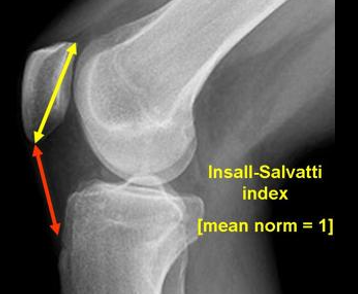

Question

A high patella in relation to the joint line is referred to as patella....

Answer

• Bhaja

• Alta

• Natantis